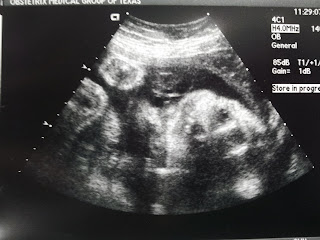

A few extra things we did this week included making homemade pasta with a friend. I had two doctor's appointments, one baby and one dentist. Everything is still looking great! Blue Rock and some of his homeschool friends painted with q-tips at our co-op. We also met a friend of mine whom I used to work with downtown for lunch.